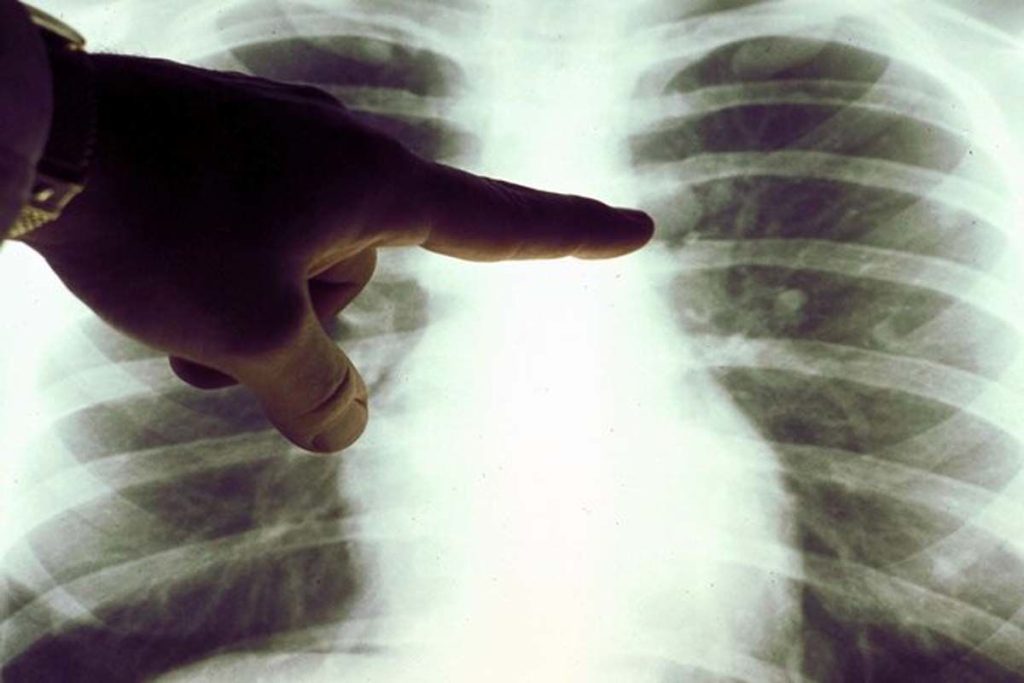

این مطالعه به سرپرستی گروهی از پزشکان و متخصصان آمریکایی در نیویورک و با عنوان «سیتیاسکن با دز کم» (LDCT) برای غربالگری افرادی که در معرض خطر بالاتر سرطان ریه هستند، استفاده شد. این نوع اسکن میتواند به یافتن نواحی غیرطبیعی در ریهها کمک کند.

دکتر «کلودیا هنشکی»، متخصص اصلی این مطالعه از دانشگاه «آیکان» نیویورک، موانع غربالگری برای این سرطان را بر میشمرد و میگوید: موانعی برای غربالگری وجود دارد که عمدتاً ناشی از این باور است که از تشعشعات بیش از حد استفاده میشود. وی با این حال این تضمین را میدهد که برای غربالگری سرطان ریه میتوان از سیتیاسکن با دز کم (LDCT) استفاده کرد که این دز حتی کمتر از ماموگرافی است.

مطالعات اخیر نشان داده است که سیتیاسکن قفسه سینه با دز پایین در تشخیص تومورهای اولیه ریه بسیار موثر است و استفاده از آن، مرگ و میر ناشی از این سرطان را تا ۲۰ درصد کاهش میدهد.

غربالگری شامل اسکن با دز کم از ریهها هر دو سال یکبار است که با تصاویری که بهزودی از سوی هوش مصنوعی تجزیه و تحلیل میشود، تلفیق میشود.